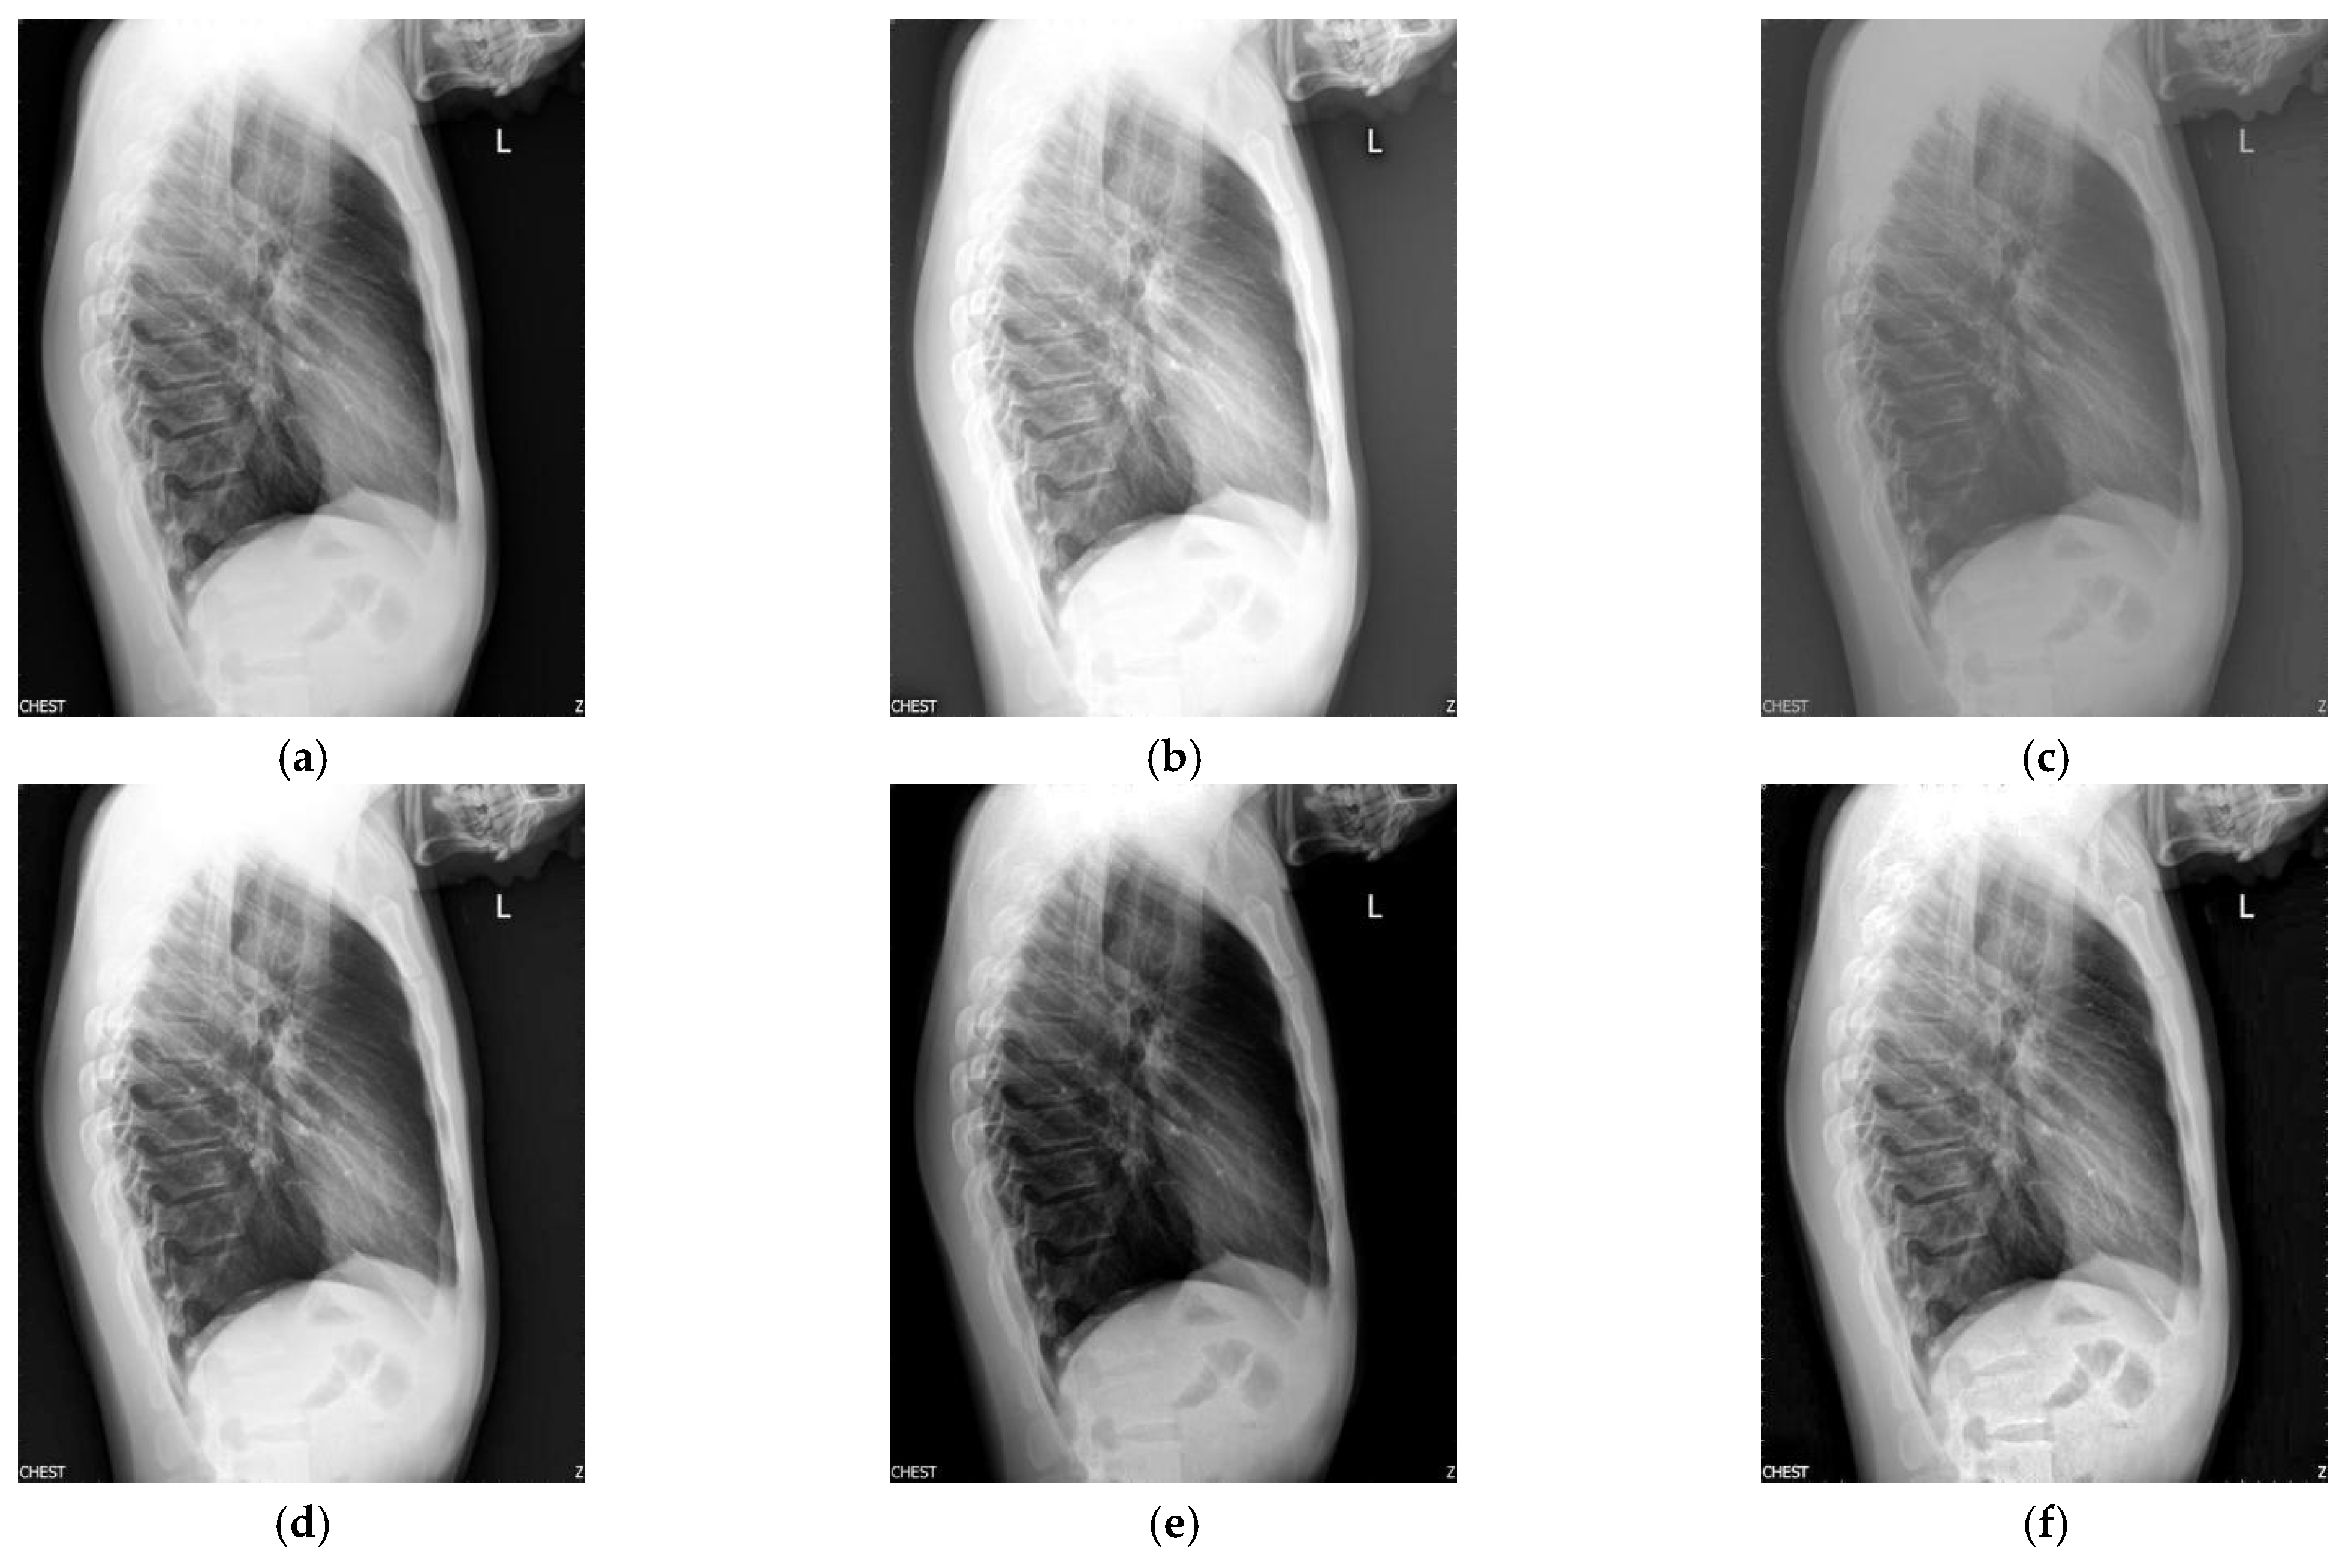

Figure 3 shows the enhancement images of eight approaches experimented on X-ray image 3. Figure 3a shows the original X-ray image 3; Figure 3b shows the enhancement result computed by McCann—the image is too bright, resulting in the loss of image details; Figure 3c shows the image achieved by RLBHE—the image is too dark, the useful information is lost; Figure 3d depicts the result achieved by RESIHE—the effect of enhancement is not obvious; Figure 3e shows the image obtained by TBCSSR—the image becomes gray and it is difficult to observe the details; the results enhanced by GDGIF, SMIPC, and FuzzyII are shown in Figure 3f–h, respectively. They are very similar and the enhancement effect is not prominent. Our method is depicted in Figure 3i—it performs well, and more details are retained. Table 3 shows the evaluation index values of the methods in Figure 3. Our method obtains the best values for all the metrics.

Figure 3.

Comparison on X-ray image 3. (a) Original image; (b) McCann; (c) RLBHE; (d) RESIHE; (e) TBCSSR; (f) GDGIF; (g) SMIPC; (h) FuzzyII; (i) Proposed method.

Table 3.

The metric data of eight methods on X-ray image 3.